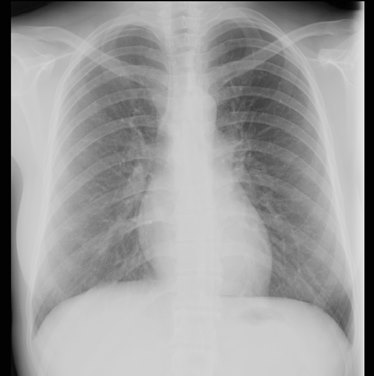

Os autores apresentam o caso de uma doente do sexo feminino, com 20 anos, que recorreu ao serviço de urgência por lesões cutâneas máculo-papulares, avermelhadas, dolorosas e pruriginosas, coalescentes em certas áreas e localizadas sobretudo ao nível dos membros inferiores (figuras 1, 2 e 3), mas também na região dorsal e membros superiores. A doente não apresentava antecedentes pessoais relevantes ou toma de medicação habitual. Negava presença de febre mas referia artralgias, com cerca de 2 meses de evolução, sobretudo nos joelhos, com rigidez articular e compromisso funcional coincidindo, geralmente, com as lesões cutâneas. Descrevia ainda adenopatias cervicais ocasionais e, nos períodos em que apresentou as lesões cutâneas, foram identificadas adenopatias inguinais, indolores, bilaterais e infra-centimétricas. Analiticamente apresentou um discreto aumento da velocidade de sedimentação (máximo de 20 mm/h) e uma elevação da enzima de conversão da angiotensina sérica (SACE, máximo de 67 ug/L). Realizou tomografia computorizada torácica que, numa fase inicial, não mostrou alterações sugestivas de sarcoidose mas cujo controlo radiológico posterior, evidenciou adenopatias hilares bilaterais (figura 4), sobretudo ao nível hilar direito. Constatou-se associadamente, hiperventilação em repouso, no estudo funcional respiratório. Foi excluída patologia hematológica e infeciosa, nomeadamente, tuberculose, como etiologias possíveis de granulomas não caseosos e adenopatias múltiplas. Assim, e perante a indiscutível presença da tríade clássica a que acima se aludiu, foi diagnosticada a SL, optando-se por dispensar confirmação histológica. Considerando a gravidade das queixas articulares, foi iniciada prednisolona 10mg/dia associada a anti-inflamatórios não esteroides, consoante necessidade, durante 2 semanas. Constatou-se resolução total das lesões cutâneas e melhoria franca das queixas álgicas ao fim de 4 semanas. Um ano após o diagnóstico, a doente permanece assintomática, sem recidivas das lesões cutâneas, com parâmetros inflamatórios negativos apesar de valores de SACE no limite superior do normal mantendo, por essa razão, seguimento em consulta.